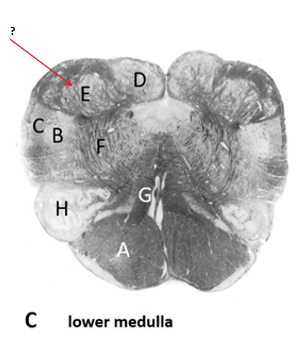

Name this, state its function and pathway[5 marks].

Pyramid.

Name this and state its function.

Nucleus Gracilis.

Name this , state its function, pathway and tract its involved to.

Nucleus cuneatus.

Cuneatus receptors–>Dorsal roots–>nucleus cuneatus–>Thalamus–>somatosensory cortex.

Inferior olivary nucleus:

Medial lemniscus.

Name this, state its functions within their tracts, different tracts and regulators of the their tracts.

Reticular formation.

Ascending tracts:

Descending tracts:

Name this.

Spinal Trigeminal nucleus.

Spinal trigeminal tract.

Questions:

Descending pathway:

Ascending pathways: